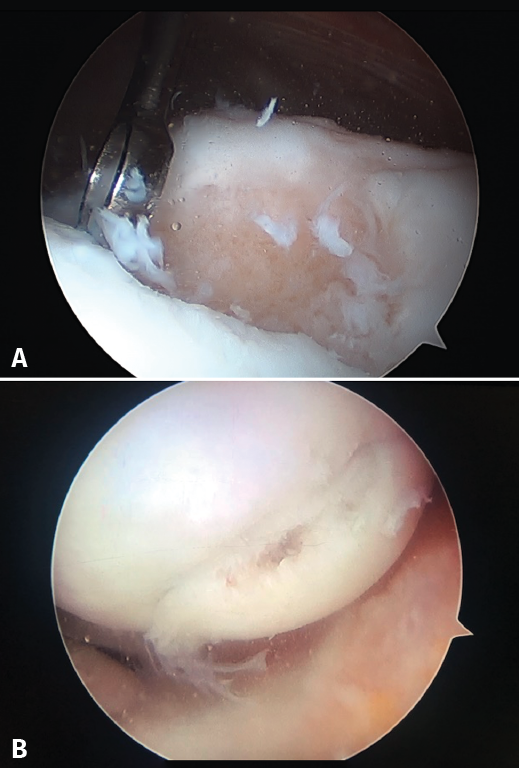

The application of ACI on a carrier or scaffold has been a great advance in the treatment of joint cartilage lesions. One of the most commonly used techniques worldwide is the matrix-assisted autologous chondrocyte implantation (MACI), in which a type I/III collagen membrane of porcine origin is used as biomaterial(24,25,26,27,28). This technique is based on a modification of the ACI procedure, involving the use of a collagen membrane that acts as a biological support in which the chondrocytes are integrated after culture(24). This technical variant is employed to cover the cartilage defect with the mentioned membrane instead of using periosteum (as a patch). An advantage of MACI is that it can be performed with arthroscopic techniques and, since no periosteum is required, surgery is simpler(29). Since in this case implantation was made with a membrane, in our centre we designed special instruments to facilitate placement of the cultured cells (Figure 7).

[[{"fid":"4539","view_mode":"default","fields":{"format":"default","alignment":""},"type":"media","field_deltas":{"8":{"format":"default","alignment":""}},"link_text":null,"attributes":{"class":"media-element file-default","data-delta":"8"}}]]

The inconvenience of this technique is that the placed cell concentration is low: 1,000,000 cells per cm2.

The results obtained with this variation of the technique have been very good, and by using the arthroscopic approach it is still possible to achieve practically complete regeneration of the joint surface in a high percentage of cases through the formation of hyaline cartilage rich in type II collagen(25,28).

This membrane, which is also used in the MACI implant, does not require the use of periosteum, and the procedure can be carried out via arthroscopy - suturing the implant to the bone tissue and sealing with fibrin glue (Figure 11).